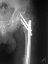

ЭОП унас нет, больной оперирован тогда, 35 дней назад, во время наркоза определена патологическая подвижность в вертельной обл, поэтому произведена остеотомия с исправлением угла, антеградный БИОС ,универсальный стержень ChM. Рентген снимки свежие фас и аксиальная. Пациент ходит с двумя костылями, ногу частично нагружает, лежа выпрямленную ногу поднимает.

На мой взгляд угол абсолютно не исправлен, а даже где-то уменьшился (106 гр. против 114), есть все условия для прорезывания шеечных винтов при нагрузке. Если открывали зону перелома, почему не выбрали в качестве импланта клинковую пластину?